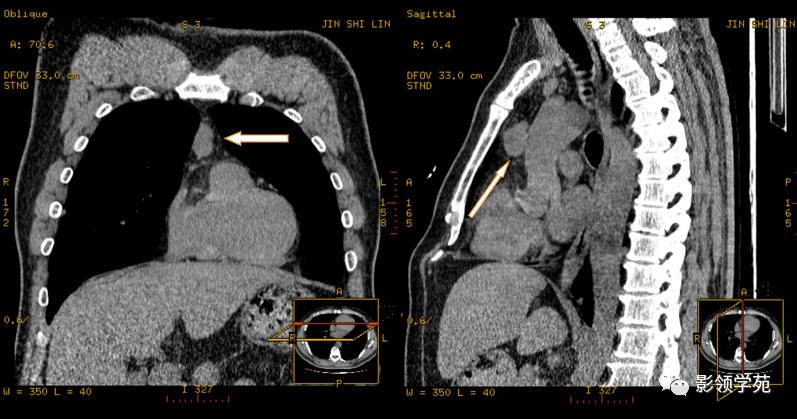

1、可以融合成块,也可以散在存在,常累计相邻多组淋巴结,淋巴结境界较清晰,如有结外浸润可边缘模糊不清。

2、淋巴结的侵犯和分布以前纵隔和气管旁组最常见,其次为气管与支气管组和隆突下组,后纵隔、纵隔下部、心旁组和胸骨后组较少见。

3、常侵犯两侧纵隔或肺门淋巴结,且呈对称性,很少单独侵犯肺门淋巴结。

4、明显增大的淋巴结,特别是融合成团的易侵犯大血管及大气管。

5、肿块很大时可出现坏死和囊性变。

6、增强扫描一般轻度到中度强化,与明显强化的血管形成鲜明对比。

淋巴结肿大融合,压迫上腔静脉,致上腔静脉狭窄

淋巴结肿大融合,轻度强化,与血管形成鲜明对比